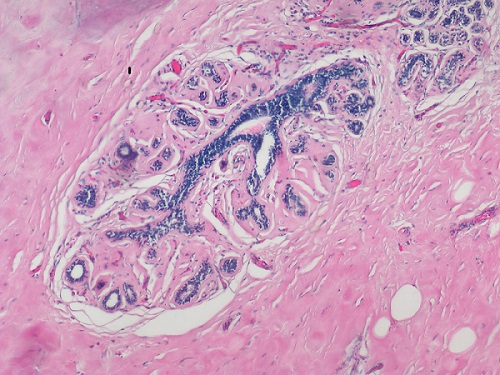

常用的染色方法是蘇木素-伊紅(Hematoxylin-Eosin)染色法,簡稱H.E染色法。這種方法對任何固定液固定的組織和應(yīng)用各種包埋法的切片均可使用。蘇木素是一種堿性染料,可使組織中的嗜堿性物質(zhì)染成藍(lán)色,如細(xì)胞核中的染色質(zhì)等;伊紅是一種酸性染料,可使組織中的嗜酸性物質(zhì)染成紅色,如多數(shù)細(xì)胞的胞質(zhì)、核仁等在H.E染色的切片中均呈紅色。

(明美生物顯微鏡搭配msx2拍攝HE染色的乳腺癌病理切片,紅色為胞質(zhì),藍(lán)色為染色體)